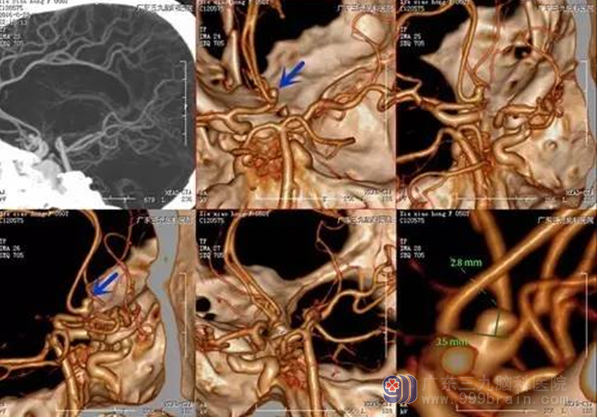

谢女士,50岁,突发爆炸性头痛1天,头颅CT示蛛网膜下腔出血,入院后行CTA提示前交通动脉瘤,完善相关检查后,行全麻下前交通动脉瘤夹闭术,术后患者病情恢复良好,头痛缓解出院。

前交通动脉瘤(anterior communicating artery aneurysm, ACoAA)是指前交通动脉的局部血管壁扩大、变薄等异常改变而产生的瘤样突起,是颅内动脉瘤常见的类型,约占所有动脉瘤的30%。好发于优势大脑前动脉A1-A2的交汇处。由于前交通动脉瘤位置深,周围解剖复杂,穿通动脉多且意义重要,血管变异复杂,动脉瘤方向多变,ACoAA是目前较难处理的颅内动脉瘤之一,若动脉瘤破裂后存在颅高压,术中也会增加动脉瘤暴露难度,良好的暴露仍需要精确的手术设计、精湛的手术技术及术者的耐心。本例患者瘤体位于前交通动脉,呈囊状凸起,方向朝前上,范围约3.5mm *2.8mm,动脉瘤破裂致蛛网膜下腔出血,暴露存在一定难度,整体手术过程顺利。